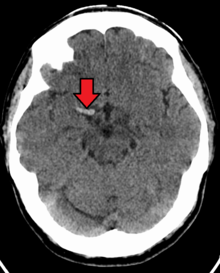

Acute thrombus in the right MCA M1 branch

A stroke is the rapid decline of brain function due to a disturbance in the supply of blood to the brain.[10] This can be due to ischemia, thrombus, embolus (a lodged particle) or hemorrhage (a bleed).[10] In thrombotic stroke, a thrombus (blood clot) usually forms around atherosclerotic plaques. Since blockage of the artery is gradual, the onset of symptomatic thrombotic strokes is slower. Thrombotic stroke can be divided into two categories — large vessel disease or small vessel disease. The former affects vessels such as the internal carotids, vertebral and the circle of Willis. The latter can affect smaller vessels, such as the branches of the circle of Willis.[citation needed]